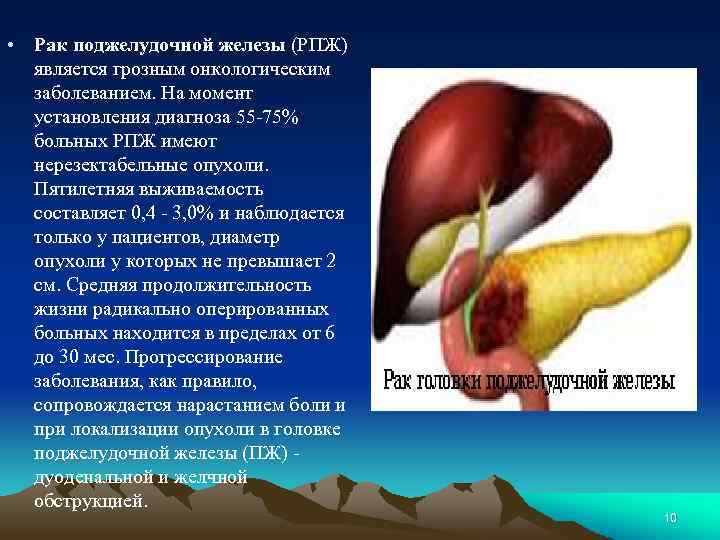

• Рак поджелудочной железы (РПЖ) является грозным онкологическим заболеванием. На момент установления диагноза 55 75% больных РПЖ имеют нерезектабельные опухоли. Пятилетняя выживаемость составляет 0, 4 3, 0% и наблюдается только у пациентов, диаметр опухоли у которых не превышает 2 см. Средняя продолжительность жизни радикально оперированных больных находится в пределах от 6 до 30 мес. Прогрессирование заболевания, как правило, сопровождается нарастанием боли и при локализации опухоли в головке поджелудочной железы (ПЖ) дуоденальной и желчной обструкцией. 10